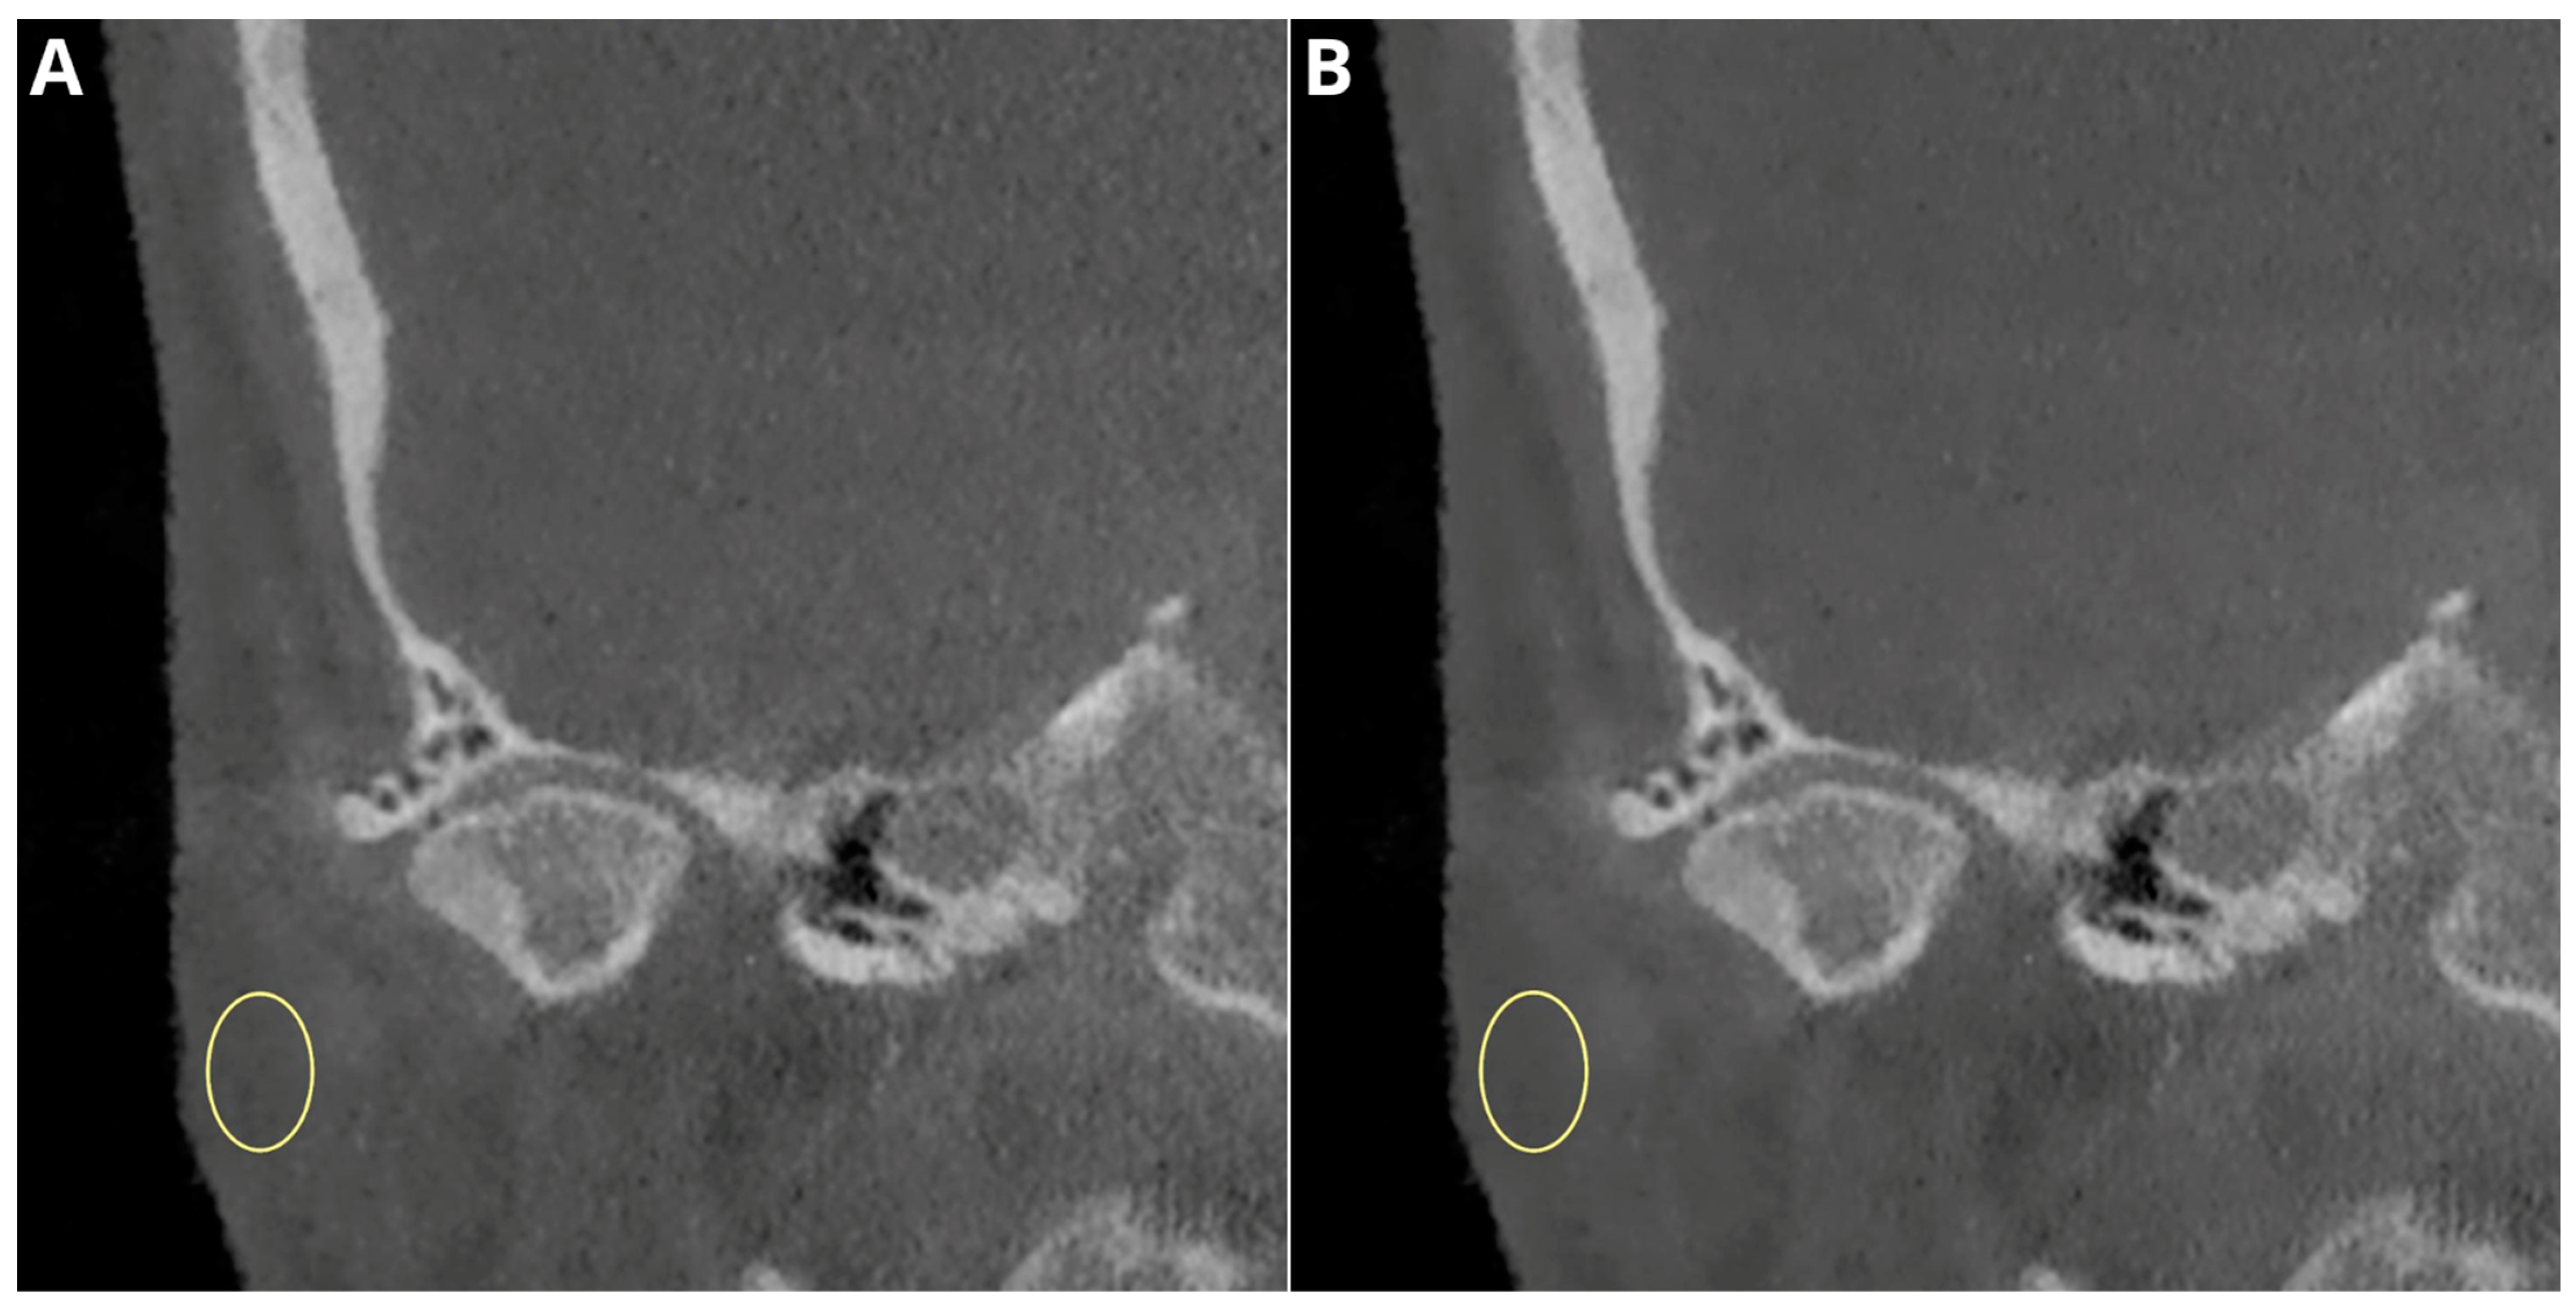

Does TMJ surgery change your face? Discover how corrective jaw surgery and TMJ treatment affect facial aesthetics, bone structure, and symmetry. Learn the potential impact of these procedures on your appearance, recovery expectations, and whether facial changes are a common side effect of addressing temporomandibular joint disorders. Understand the reality behind surgical outcomes for jaw pain relief.

Read full article: Does Tmj Surgery Change Your Face